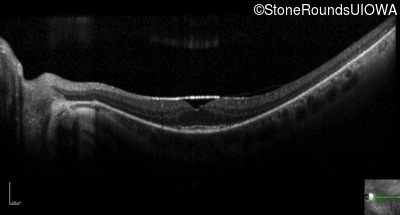

Optical Coherence Tomography - Right - 20/25 -2 sc

Exemplar / OCT Stack

OCT Stack